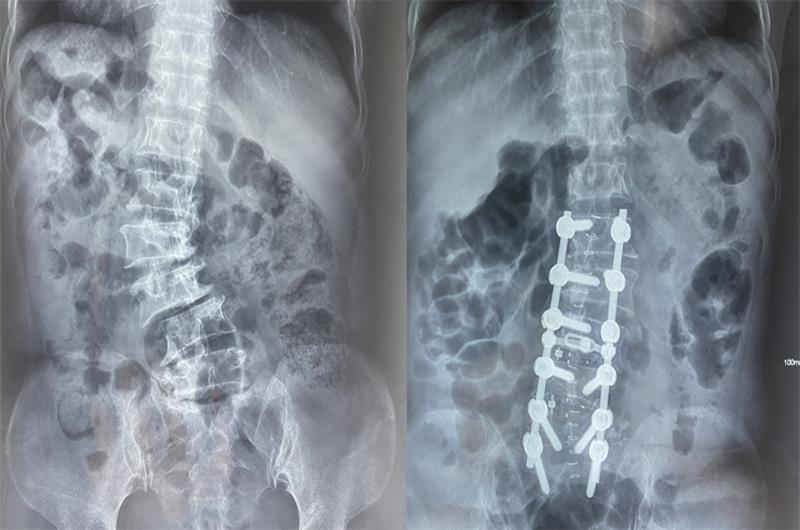

Hình ảnh cột sống bệnh nhân trước (bên trái) và sau (bên phải) khi phẫu thuật nắn chỉnh

Kết quả chụp MRI của bệnh viện cho thấy cột sống thắt lưng đoạn từ L3-L5 của bệnh nhân bị vẹo gây hẹp nặng ống sống. Đây là trường hợp biến dạng cột sống phức tạp, cần can thiệp phẫu thuật để nắn chỉnh và giải ép thần kinh nhằm giúp các triệu chứng đau nhức giảm dần và chấm dứt hẳn.

ThS-BS Trần Đức Duy Trí, Khoa Chấn thương chỉnh hình cùng ê kíp đã phẫu thuật cố định từ đốt sống L1 đến S1, chỉnh hình vẹo cột sống, giải phóng chèn ép thần kinh, khôi phục lại hình dáng giải phẫu bình thường của cột sống cho người bệnh. Sau 4 giờ đồng hồ, ca phẫu thuật thành công, tình trạng vẹo cột sống của bà Đ. được cải thiện đáng kể, đường cong cột sống đã được nắn chỉnh gần như thẳng hoàn toàn.